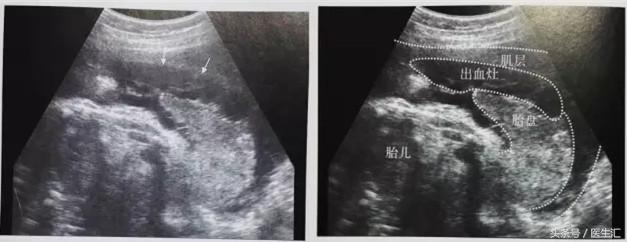

3.胎盘边缘血窦破裂:胎盘边缘胎膜与宫壁分离、隆起,胎膜下见不均质低回声。(见图7)

(图7)